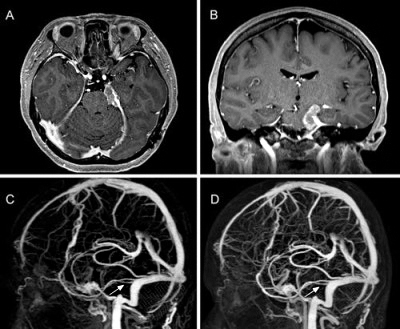

КТ Ангиография церебральных сосудов и сосудов шеи с контрастированием (болюсное усиление)

КТ ангиографии брахиоцефальных артерий один из наиболее информативных методов диагностики патологии сосудов шеи и головного мозга.

Данный метод позволяет получить информацию о форме, диаметре, наличии сужений, аневризм и мальформаций артерий, питающих головной мозг.